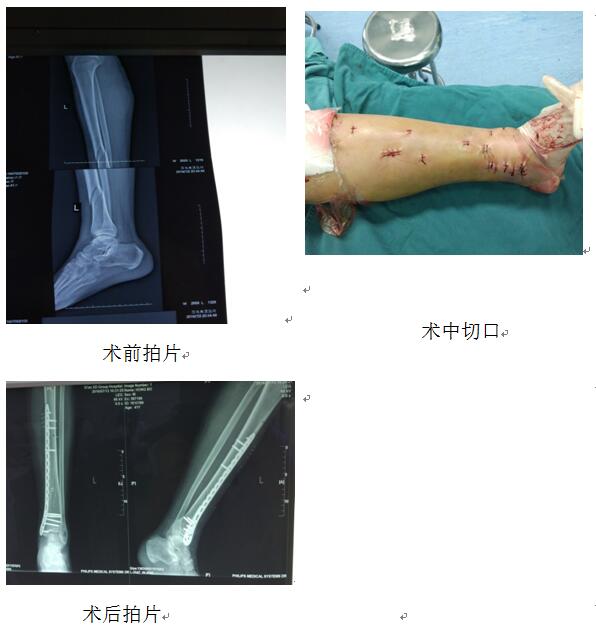

洪×,男,41歲,于2016年7月2日以“車禍致左小腿疼痛、出血、活動受限2小時余”收住我科。入院診斷:1、左脛骨粉碎骨折2、左小腿挫裂傷3、右足背裂傷并趾伸肌腱斷裂4、右足踇趾近節(jié)骨折。入院時左下肢??撇轶w:左小腿腫脹明顯,小腿中下1/3處成角畸形。小腿上段脛前有一約6cm長斜行裂傷,深達骨質(zhì),創(chuàng)面軟組織挫傷重,傷口污染明顯。入院后我科值班醫(yī)生行開放傷清創(chuàng)縫合、肌腱探查吻合術(shù),術(shù)后患肢支具制動及對癥治療。根據(jù)傳統(tǒng)治療方案,至少傷后半月皮膚條件明顯改善才可行骨折切開復位內(nèi)固定手術(shù)治療,且因錯過骨折治療的最佳時機,并且術(shù)中長切口、廣泛剝離骨膜也為以后骨折的愈合留下了隱患。在我科張富軍主任的帶領下,于患者傷后第10天我科即開展MIPPO技術(shù)為患者施行經(jīng)皮微創(chuàng)左脛骨骨折閉合復位鋼板內(nèi)固定術(shù)。術(shù)中閉合復位骨折后僅在左小腿遠近端行2-3cm小切口經(jīng)骨膜上插入鋼板,皮膚刺孔上螺釘固定骨折。手術(shù)時長約1小時,獲得治療最佳效果。以下就是患者術(shù)前、術(shù)后拍片及切口情況圖片。此類手術(shù)的開展也標志著我科在MIPPO技術(shù)方面達到了國內(nèi)先進水平。